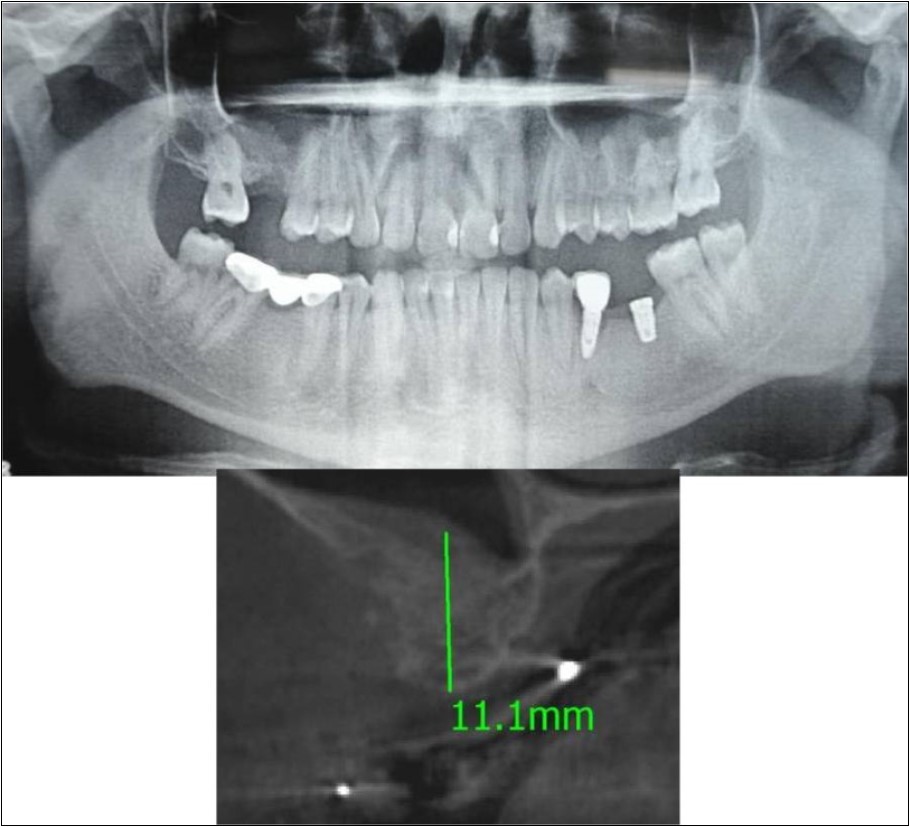

Case Report 4:

A 19 years old young female patient reported to the Department of Oral and Maxillofacial Surgery, D.A.P.M.R.V Dental College and Hospital seeking options for replacement of her missing right and left upper first molars with a fixed prosthesis as she was uncomfortable with the removable partial denture i.r.t 16 and 26. The teeth were extracted 6 months ago because of gross loss of crown structure and poor prognosis for root canal treatment. Patient was also undergoing fixed orthodontic treatment for proclined upper anteriors. Patient did not give history of any existing sinus pathologies. All possible rehabilitative options were explained to the patient and a treatment plan of replacement of missing teeth with implant supported prosthesis using two dental implants was finalized.

Clinical and Radiological Assessment:

1.Partially edentulous maxillary arch with missing 16 and 26;

2.Increased pneumatisation of right and left maxillary sinus;

3.Height of available bone-

16 region: 6.5mm;

26 region: 6.2mm;

4.Transverse thickness of available bone (CBCT evaluation)-

16 region: 8.3mm;

26 region: 10.5mm;

5.Fixed orthodontic appliance;

6.Inter-ridge space adequate to place implant (11mm).

Treatment:

Patient underwent the procedure of indirect sinus elevation using sinus osteotomes in relation to 26 region. Calcium phosphosilicate putty was dispensed as the graft material through the crestal osteotomy site to maintain the elevated sinus membrane followed by placement of 5 x 10mm dental implant under local anaesthesia and strict aseptic protocols. The implant was allowed to osseo-integrate for a period of six months during which the patient was followed-up periodically and was assessed for peri-implantitis, crestal bone loss and mobility. Patient was taken-up for direct sinus elevation via lateral window approach for sinus augmentation i.r.t 16 region. Under aseptic conditions and local anaesthesia, lateral wall of maxilla was exposed after muco-periosteal flap elevation. A window was created of 1cm diameter corresponding to apical aspect of 16. Sinus membrane was identified and elevated using sinus elevators and reamers without perforating the lining. Once the sinus membrane was elevated, phosphosilicate putty was dispensed through the lateral osteotomy site as the graft material to achieve an augmentation of 1cm assessed clinically and confirmed using post-operative OPG. At the end of 6 months, a repeat CBCT scan was advised to evaluate the increase in bone height. (Figure 13a,b, pre-treatment; Figure 14a,b, post-treatment)

Figure 13.(a,b) Pre-treatment OPG and cross section of CBCT showing residual alveolar bone height for Case No.4;

Figure 14.(a,b) Post-treatment OPG and cross section of CBCT showing residual alveolar bone height for Case No.4;